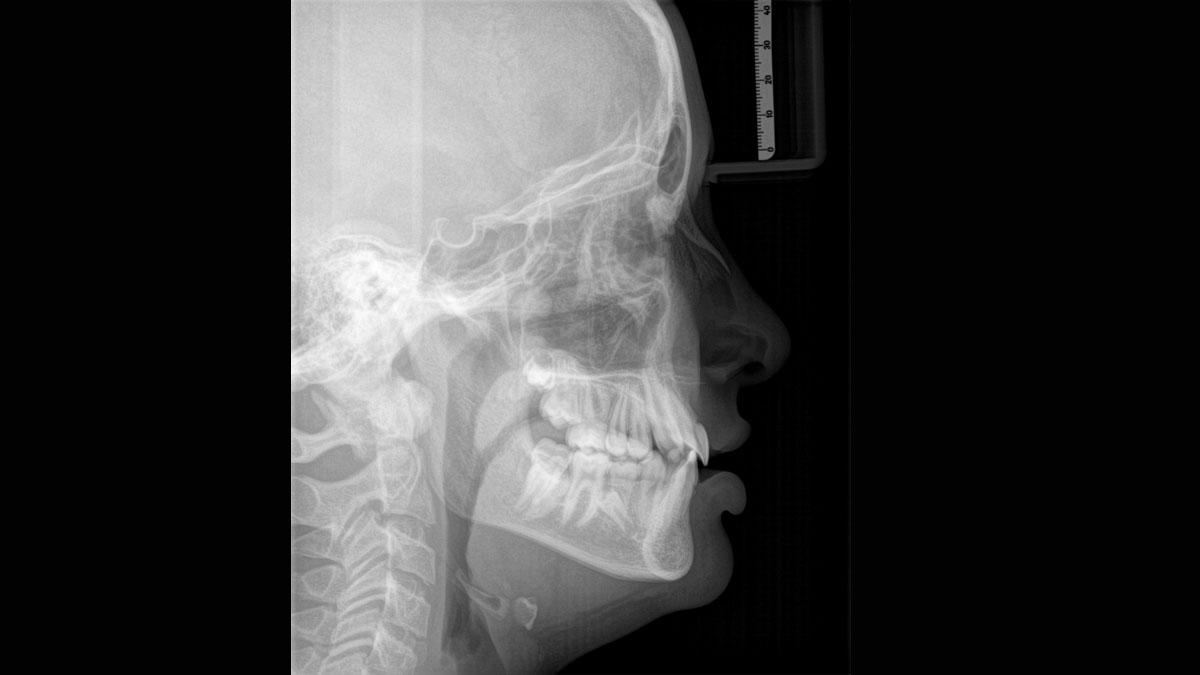

Der 2D/3D Power Performer Orthophos SL ist eine großartige Wahl für alle, die einfach mehr wollen. Der integrierte Direct Conversion Sensor (DCS) wurde für anspruchsvolle Bildqualitätsstandards entwickelt und bietet detaillierte Daten. Der intelligente Autofokus liefert automatisch fokussierte Panoramabilder mit hervorragender Gesamtschärfe. Orthophos SL bietet höchsten Bedienkomfort durch automatische Positionierung, eine anwenderfreundliche, intuitive Bedienung mit dem EasyPad und ein individuell einstellbares Umgebungslicht für ein exklusives Erscheinungsbild.

Der Autofokus erzeugt aus mehreren tausend Einzelbildern automatisch eine beeindruckende scharfe Panorama-Röntgenaufnahme

Der Direct Conversion Sensor (DCS) hat den Standard der Panorama-Bildgebung neu definiert. Röntgenstrahlen werden direkt in elektrische Signale umgewandelt – im Gegensatz zu herkömmlichen Systemen gibt es keinen Signalverlust durch Lichtumwandlung, was eine verbesserte Bildgebung ermöglicht. Das Ergebnis sind Bilder mit einer sehr hohen Schärfe, selbst bei niedriger Dosis.

Eine Röntgenaufnahme muss sofort diagnostizierbar sein. Der Autofokus hilft dabei erheblich. Orthophos SL erfasst mehrere tausend Einzelbilder in einem Zyklus und erkennt automatisch scharfe Bereiche, um ein gleichmäßig scharfes Gesamtbild zu erzeugen. Der intelligente Autofokus erfordert keine manuellen Arbeitsschritte vor und nach der Erfassung.